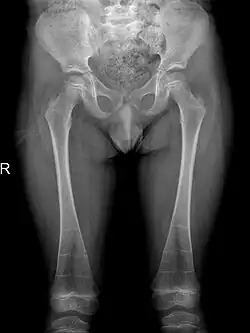

It is also reported that individuals may also have pelvic abnormalities. This includes the development of narrow iliac wings, as well as widened femoral necks. However, incidence of both symptoms are rare in patients with DSS, occurring in less than 30% of cases.[6][7]

The occurrence of DSS also leads to deformities of the limbs. 80% of patients reported with abnormalities of the metaphysis such as metaphyseal flaring, radiolucent metaphyses, abnormal metaphyseal trabeculation, which is abnormal trabecula patterns in the metaphyseal region, and epimetaphyseal sclerosis. Other limbic abnormalities include progressive bowing of long bones, which is present in rare cases.[6][7]

Sclerosis of epiphyses, diaphyses, and metaphyses with increased radiolucency are key characteristics of the disease.[18] In addition, mottled metaphyseal sclerosis and widening are also present in patients.[4][9] Development of irregular patchy sclerosis along the bone can also be identified,[9] as well as metaphyseal flaring evolve towards Erlenmeyer flask deformity with nonuniform patches of sclerosis, which are especially prevalent in older patients.[10]

The metadiaphyses, a portmanteau of the metaphysis and diaphysis,[20] are bulbous and expanded with bowing and relative radiolucency. The expanded regions are also sclerotic and gives the characteristic bone-in-bone appearance.[4]